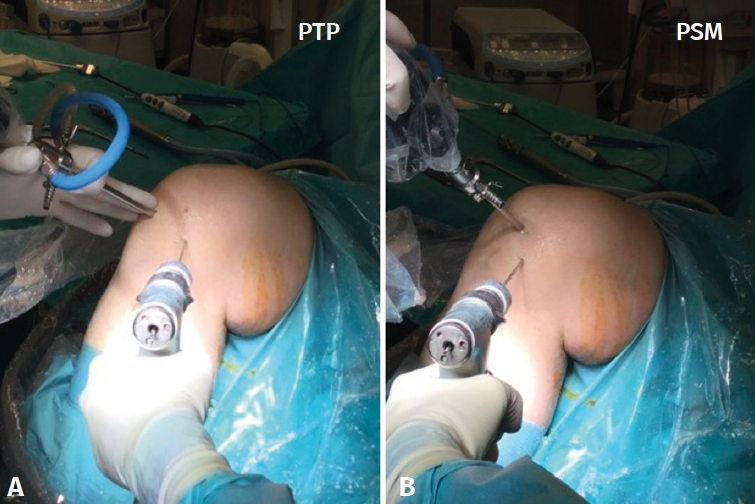

Pueden ser necesarios portales accesorios que permitan una visualización completa de la zona en la que deben realizarse los túneles femoral y tibial, ya que pueden proporcionar información adicional útil. Habitualmente, se utiliza el portal superomedial (PSM) a nivel parapatelar interno, pero también se pueden considerar otros portales, como el transpatelar (PTP), como podemos ver en las Figuras 1A y 1B. Por lo que sabemos, no existen descripciones comparativas previas con respecto a la posición del TF, teniendo en cuenta si el portal de visualización utilizado fue el PTP o el PSM.

El procedimiento se realizó bajo anestesia raquídea con el paciente en decúbito supino. Se utilizó un soporte de piernas estándar y el cirujano se colocó frente a la rodilla del paciente. Durante la cirugía, se mantiene un torniquete de expresión entre 300 y 350 mmHg en función de la presión arterial sistólica del paciente. En todos los casos se realiza una artroscopia exploratoria utilizando los portales de trabajo que pueden verse en la Figura 2 para evaluar la presencia de lesiones intraarticulares concomitantes que puedan abordarse. Los portales PSM o PTP se utilizan para realizar la reconstrucción del LCA. El autoinjerto (tendones isquiotibiales) se obtuvo mediante una miniincisión (4 cm) sobre el punto transversal del peroné(9). El punto transversal del peroné toma como referencia el cuello del peroné, trazando una línea horizontal en dirección medial, 2,5 cm medial a la tuberosidad tibial anterior. Los tendones se duplican o triplican en función de su diámetro y longitud, por lo que el diámetro final del injerto oscila entre 8 y 10 mm.

Las referencias anatómicas para el portal de artroscopia de rodilla PSM implican el posicionamiento del portal por encima y ligeramente medial al borde medial de la rótula a lo largo de la línea articular. Sin embargo, para el PTP el portal se coloca estratégicamente a través del tendón rotuliano en el espacio intercondíleo, lo que proporciona una visualización frontal, ya sea centralmente o a lo largo del tendón rotuliano, y se coloca dentro del espacio intercondíleo, entre los cóndilos femorales. La visualización artroscópica del cóndilo femoral desde el PTP puede verse en la Figura 3A. La visualización artroscópica del cóndilo femoral desde el PSM puede verse en la Figura 3B.